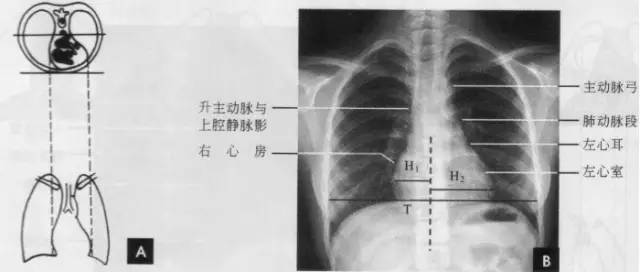

(一)后前位

正常心影2/3位于中线左侧,1/3位于右侧,心尖指向左下,心底部朝向右后上方,形成斜的纵轴。后前位心脏大血管有左右两缘:心右缘分为两段,上段为升主动脉与上腔静脉的总合影,在幼年和青年人边缘主要为上腔静脉影向上延伸,在老年人常见纡曲延长的升主动脉影突出于上腔静脉边缘之外;心右缘下段为右心房所构成,有时在心瞩角内可见一向外下方倾斜的三角形影,为下腔静脉攻肝静脉影,深吸气时明显。心左缘分为三段,上段为主动脉弓;中段为肺动脉主干,但偶尔可为左稀动脉构成,称肺动脉段或心腰,此段较低平或稍突出:下段由左心室构成,左心室在下方形成心尖。左心室与肺动脉之间有长约10cm的一小段,由左心耳构成,正常时不能与左心室区分。透视下左心室与肺动脉段的搏动方向相反,两者的交点称相反搏动点,该点上下两侧心缘里“翘翘板”样运动,该点位置是衡量左右心室增大的一个重要标志。肥胖人左心膈角常有脂肪垫充填,为密度较低的软组织影。后前位能了解心胸及肺循环概况,正常人心(h1+h2)胸(t)比率不大于0.5(如下图)。